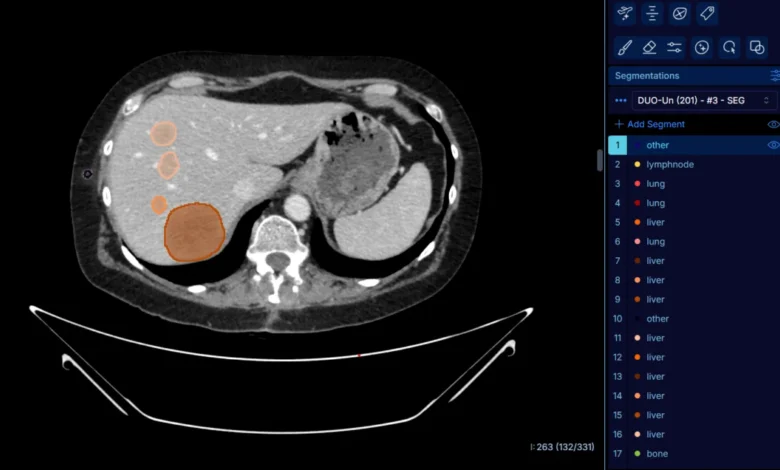

DuOnco Unity is built upon a sophisticated deep-learning algorithm trained on a massive scale. To achieve the necessary accuracy, researchers and radiologists annotated approximately 287,000 individual lesions to train the AI. This extensive dataset allows the algorithm to automatically detect and segment tumors and metastases in three dimensions across thoraco-abdomino-pelvic (TAP) CT scans—the most common imaging modality for monitoring solid cancers.

Unlike existing AI tools that focus on a single organ, DuOnco Unity is multi-organ and multi-anatomical. It analyzes the entire thorax, abdomen, and pelvis in a single pass. One of its most distinguishing features is its ability to identify and measure lymph nodes, which are among the most common sites for metastasis but are notoriously difficult to assess consistently using manual methods.